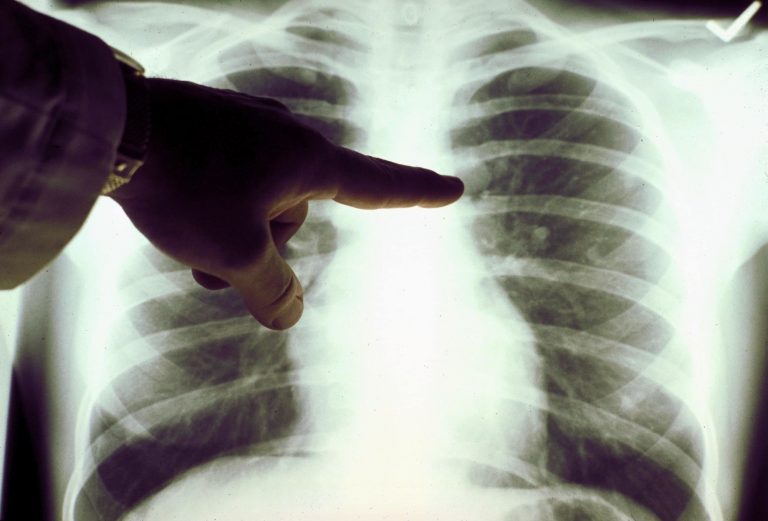

Хотя штамм «омикрон» менее патогенен, чем предыдущие и даже, по ряду исследований, почти не поражает легкие, успокаиваться рано.

По словам Александра Горелова, «омикрон», несмотря на высокую скорость распространения, до сих пор не вытеснил «дельту», которая вызывает тяжелые пневмонии и другие осложнения, приводящие к смерти заболевших.